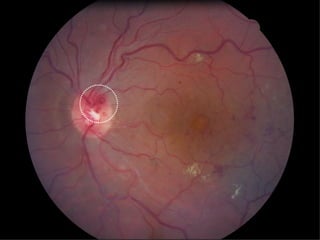

Les occlusions veineuses rétiniennes (OVR) touchent entre 6.000 et 60.000 nouveaux patients par an, avec un âge moyen de diagnostic de 57 ans pour les OVR et 65 ans pour les autres formes. Les causes et l'évolution de la maladie sont souvent imprévisibles, avec des traitements divers allant des médicaments à la chirurgie, mais les complications comme l'œdème maculaire demeurent fréquentes. Les traitements potentiels comme les injections intra-vitréennes peuvent entraîner des effets indésirables, dont un risque accru de cataracte.